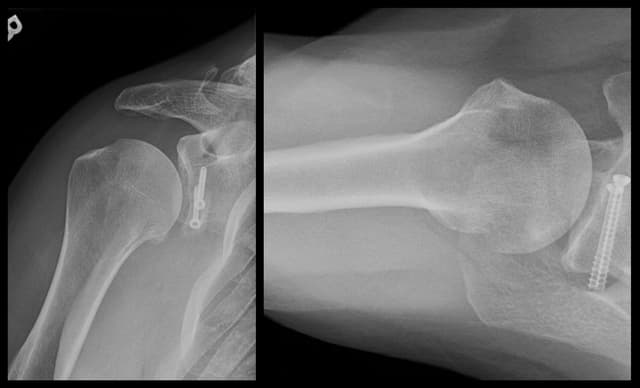

Glenoid Reconstruction with Allograft

Post-op